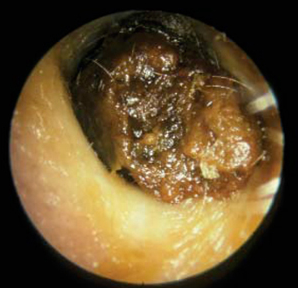

2. Earwax Blockage

Impacted wax can irritate the ear canal and eardrum.

- Wax removal